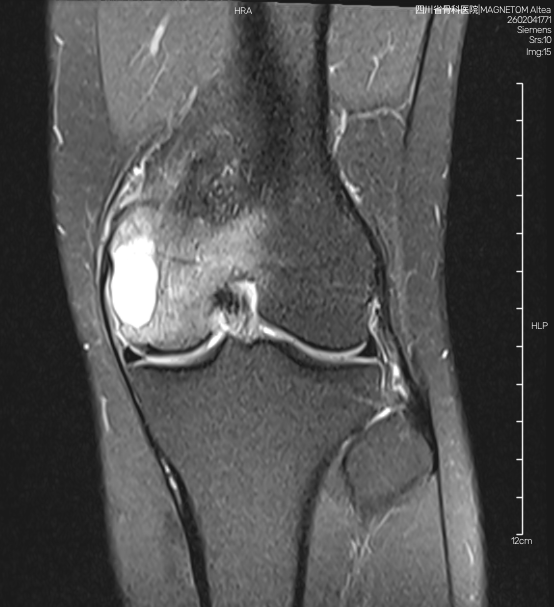

一中老年女性患者,穿刺确诊股骨远端软骨肉瘤。影像学可见膨胀性生长、骨质破坏、病灶内钙化影。此患者根据病理结果常规需行股骨肿瘤膝假体置换,需切除膝关节内外侧副韧带及前后交叉韧带等稳定装置,手术创伤大,术后康复时间长。经科室讨论并结合患者家属意见,评估该患者具备保留膝关节的条件,遂采用 3D 打印定制化假体行保关节假体重建,最大限度保留膝关节稳定结构,实现早期快速康复。

影像学可见病灶